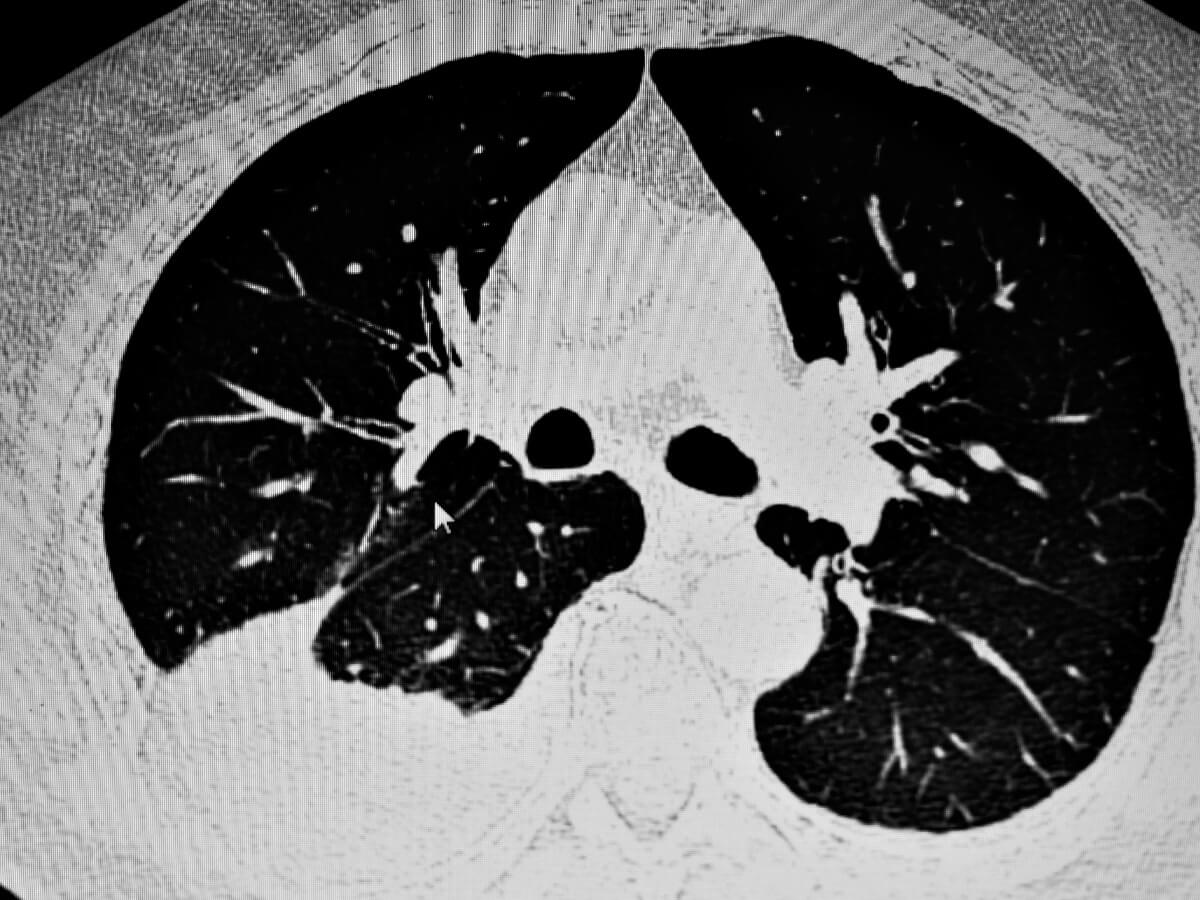

Una vez se sospecha de un problema respiratorio, se suele recurrir a los rayos X para ver de forma directa la situación patológica en el animal. Los ultrasonidos pueden ser útiles, sobre todo cuando la cantidad de fluido acumulado en la cavidad pleural es muy baja.